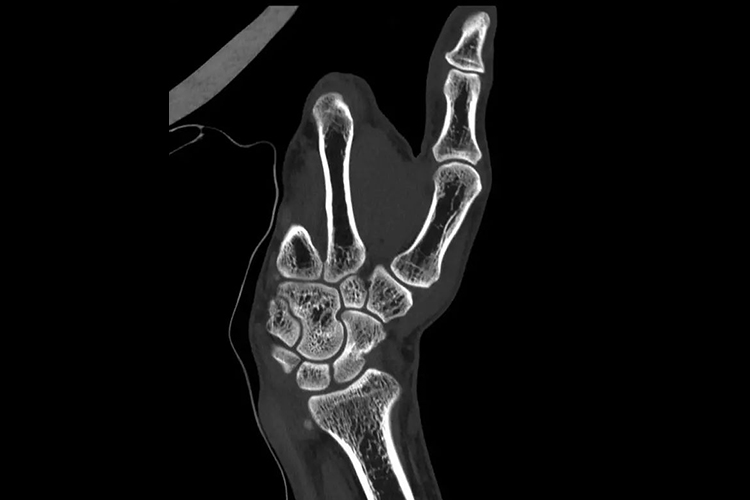

正常成人手骨在CT上可见其形态完好,位置正常,由腕骨、掌骨和指骨构成。腕骨共8块,包括手舟骨、月骨、三角骨和豌豆骨、大多角骨、小多角骨、头状骨和钩骨;掌骨共5块,包括第1-5掌骨;指骨共14块,拇指有2节指骨,其余各指均为3节,分别为近节、中节、远节指骨。手部CT通过CT后处理技术,可清晰看到各部分组织结构。